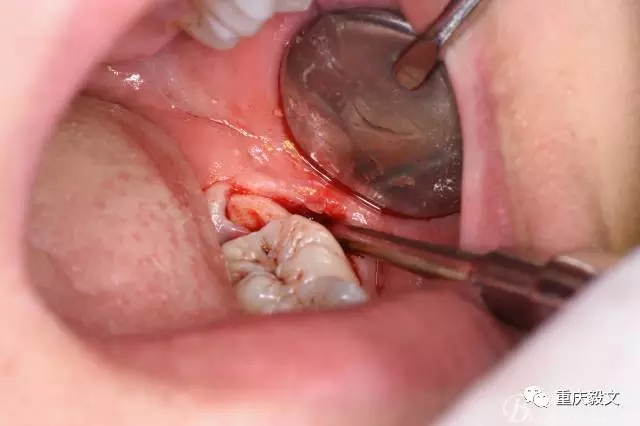

圖7.高速渦輪鉆分牙

圖8.先從頸部橫斷38

圖9.再把38牙冠近遠(yuǎn)中縱斷